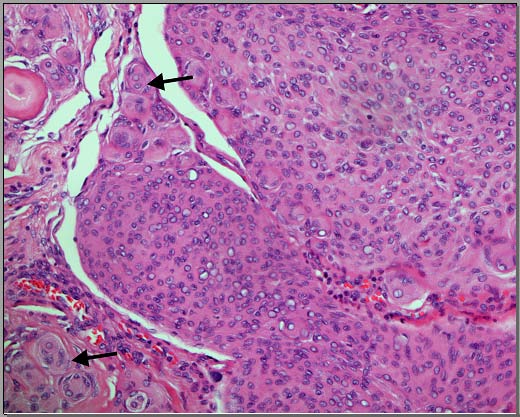

The results obtained by the ten participating pathologists and the two neuropathologists are summarized in Table 1. The kappa score for interobserver agreement between the ten anatomical pathologists was 0.53 (95 % CI for free-marginal kappa [0.32, 0.74]) with an overall agreement percent of 68.44%. The kappa score for interobserver agreement between the two neuropathologists was 0.55 (95 % CI for free-marginal kappa 0.1, and 1) with an overall agreement percent of 70%. Both kappa scores are in keeping with above chance "intermediate to good" agreement (7). The cases that showed 100% agreement were three cases. Two cases were WHO grade I. The third case was WHO grade II (Case 2, Figure 1). The latter was the only meningioma from the selected cases that showed focal necrosis. Another five cases were graded as either WHO grade I or WHO grade II by the reviewers. These cases were showing a variable degree of small cell change, lack of pattern, and cellularity (Figure 2).These cases did not show features of necrosis or prominent nucleoli. Two cases (Cases 8 and 9) were labelled as WHO grade II by the majority of the reviewers. However, in each one of them, two reviewers labelled them as WHO grade III (Figure 3). In their opinion, the reason for such designation was the focal presence of sarcomatoid morphology.